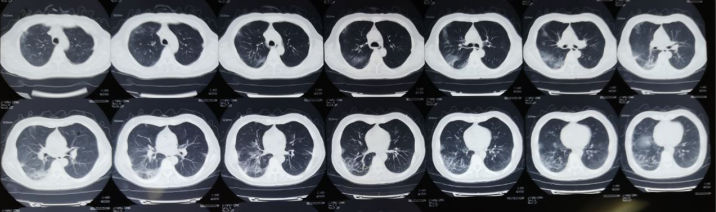

胸部CT:2021年10月21日外院胸部CT可见双肺下叶背段及基底段出现间质性改变(图1)。10月29日复查胸部CT可见双肺磨玻璃样改变较前明显加重,双侧出现少量胸腔积液(图2)

1  患者胸部CT(2021-10-21)